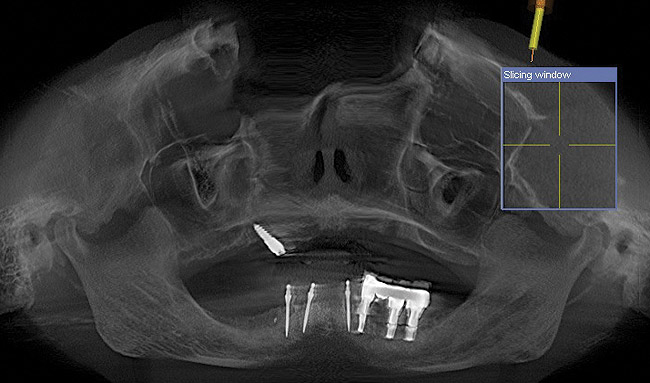

The patient was scanned with a cone beam CT scan while wearing a radiopaque scanning appliance based on her new treatment denture. Horizontal bone augmentation was confirmed radiographically, and both grafted sinuses resulted in satisfactory bone quantity for implant placement. Vertical augmentation was not attempted because of the patient’s unwillingness to forego her removable prosthesis for any period of time. Therefore, shorter implants were treatment-planned, resulting in the placement of eight implants, rather than fewer—such as six—implants, to support a full-arch fixed prosthesis. Because adequate bone and keratinized mucosa were present, a flapless, computer-guided implant insertion was performed (Figure 18). After removal of the surgical guide, placement of all eight implants could be inspected (Figure 19). Post-placement periapical radiographs are shown in Figure 20 and Figure 21.

Figure 18  Flapless, computer-guided implant insertion.

Figure 18

Figure 19  Removal of surgical guide enabled inspection of implant placements.

Figure 19

Figure 20  Post-placement periapical radiographs.

Figure 20

Figure 21  Post-placement periapical radiographs.

Figure 21